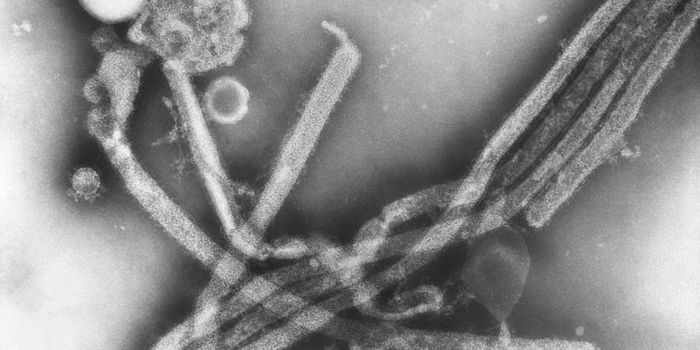

FEB 11, 2022MicrobiologyEbola virus has caused several major outbreaks in recent decades. Its high death rate and disturbing symptoms have made ...